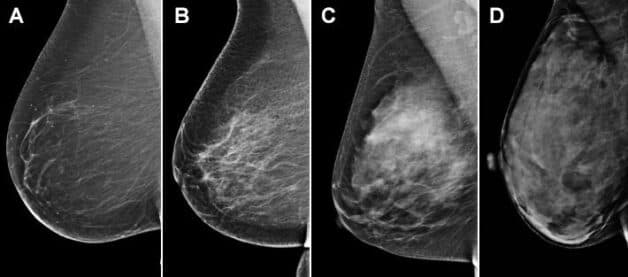

BIRADS là hệ thống dữ liệu và báo cáo hình ảnh vú được Hiệp hội điện quang Mỹ (ARC) đưa ra nhằm mã hóa các tổn thương trên siêu âm, chụp X-quang, MRI vú theo nguy cơ ung thư. Hệ thống này bao gồm 7 thang điểm đánh giá từ 0-6.

– BIRADS 4: Bất thường nghi ngờ ác tính, không chắc giống ung thư nhưng có thể là ung thư, nên xem xét sinh thiết.

– BIRADS 4A: Khả năng ung thư hóa thấp (2-10%)

– BIRADS 4B: Khả năng ung thư hóa vừa phải (10%-50%)

– BIRADS 4C: Khả năng mắc ung thư cao (50%- 95%), nhưng không cao bằng BIRADS 5.